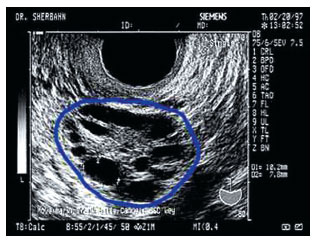

3.超声下发现多囊卵巢

如果在超声检查是发现卵巢上的卵泡数单侧超过12个(同一个切面),那么就算是多囊卵巢。

当然诊断需要有超声医生的技术上的要求。但是很多医生在写报告的时候并不写他看到的卵泡的数字,有时候会比较模糊的写多囊。这种时候,作为患者当时可以和医生沟通一下,了解是否达到诊断标准。

图片来源于网络